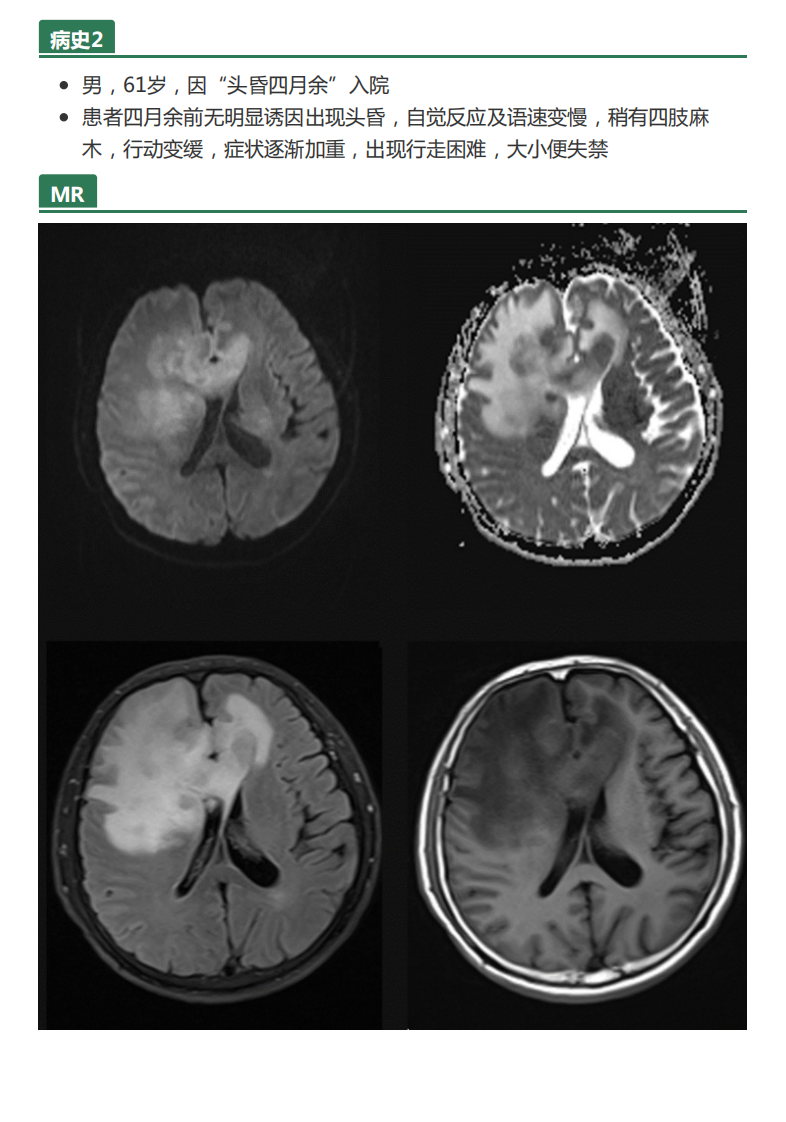

中大放射

20210608_2【晨读结果公布】2021.06.07神经系统疾病——病例1:间变型少突胶质细胞瘤;病例2:PCNSL;病例3:胼胝体急性梗死.pdf